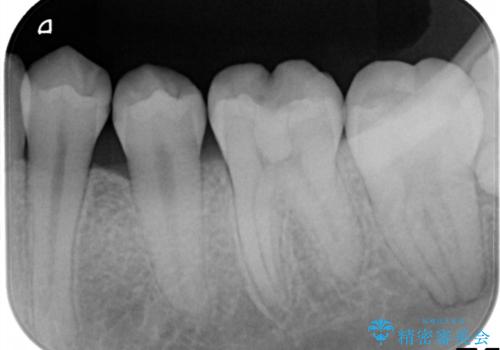

- 左下の第1・第2小臼歯の接触面にカリエスを認めました。

隣接面のため肉眼での確認が難しく、レントゲンにて診断を行ったのち、

マイクロスコープを使用して虫歯を丁寧に除去。

歯質の保存と適合精度、そして審美性を考慮し、セラミックインレーによる修復を行うこととしました。